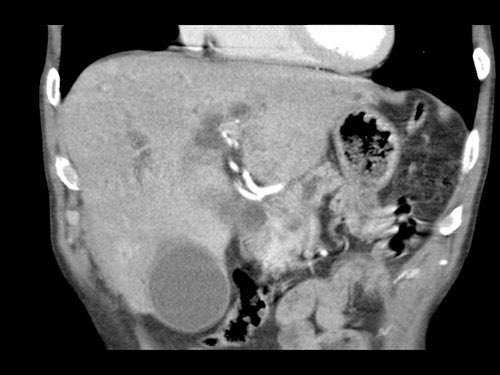

Tái tạo mặt phẳng coronal cho thấy một khối u lớn xuất phát từ cổ tụy với kiểu phát triển xâm lấn (hình A và B).

Có hiện tượng bao quanh động mạch thân tạng 360º (mũi tên trong A).

CT axial MIP tại mức động mạch thân tạng cho thấy hẹp động mạch gan chung bị bao quanh (mũi tên), rất nghi ngờ xâm lấn.